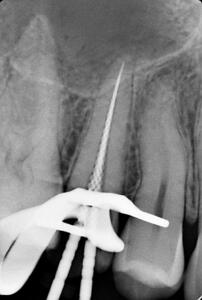

Клинические случаи в эндодонтии